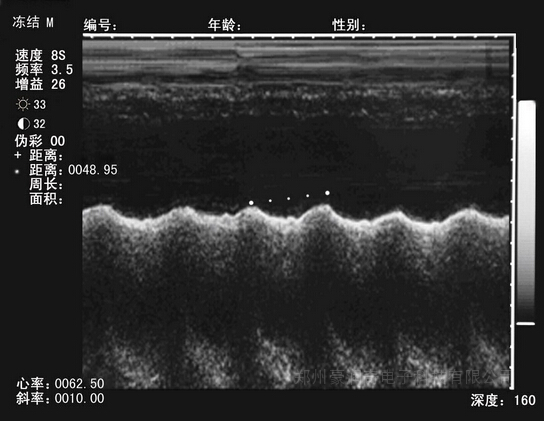

测胎儿心率主要找准心脏的位置,其次要确定主机处于B/M或M模式且冻结的状态,这个时候按下“测量/9”键,屏幕上会出现距离计算菜单(按距离测量方式测量2个心动周期波峰之间的距离,光标落在距离后,同时屏幕上还出现测量的初始光标“+”,此时选择按“←/2”“→/3”“↑/1”“↓/4”四键,可移动“+”光标,确定好初始位置后,按“OK”键,距离计算菜单消失,此时按“←/2”“→/3”“↑/1”“↓/4”四键可移动测量的第二光标,并自动在距离后显示距离测量结果和在屏幕的下方自动显示心率结果和斜率结果。

如果此时想固定第二光标激活第1光标,按“OK”键后,第二光标固定,此时选择按“←/2”“→/3”“↑/1”“↓/4”四键,第1光标移动。反复按“OK”键可反复激活第1和第二光标0第1把尺测量完毕后,如需进入第二把尺的距离测量,先按“取消”键,再按“测量/9”键后,按上述的第

一把尺的测量方法进行第二把尺的距离测量即可,两把尺的距离测量完毕后,如需再测量,需按“取消”后再按“倍率/清屏”键,重复心率和斜率的计算步骤即可。